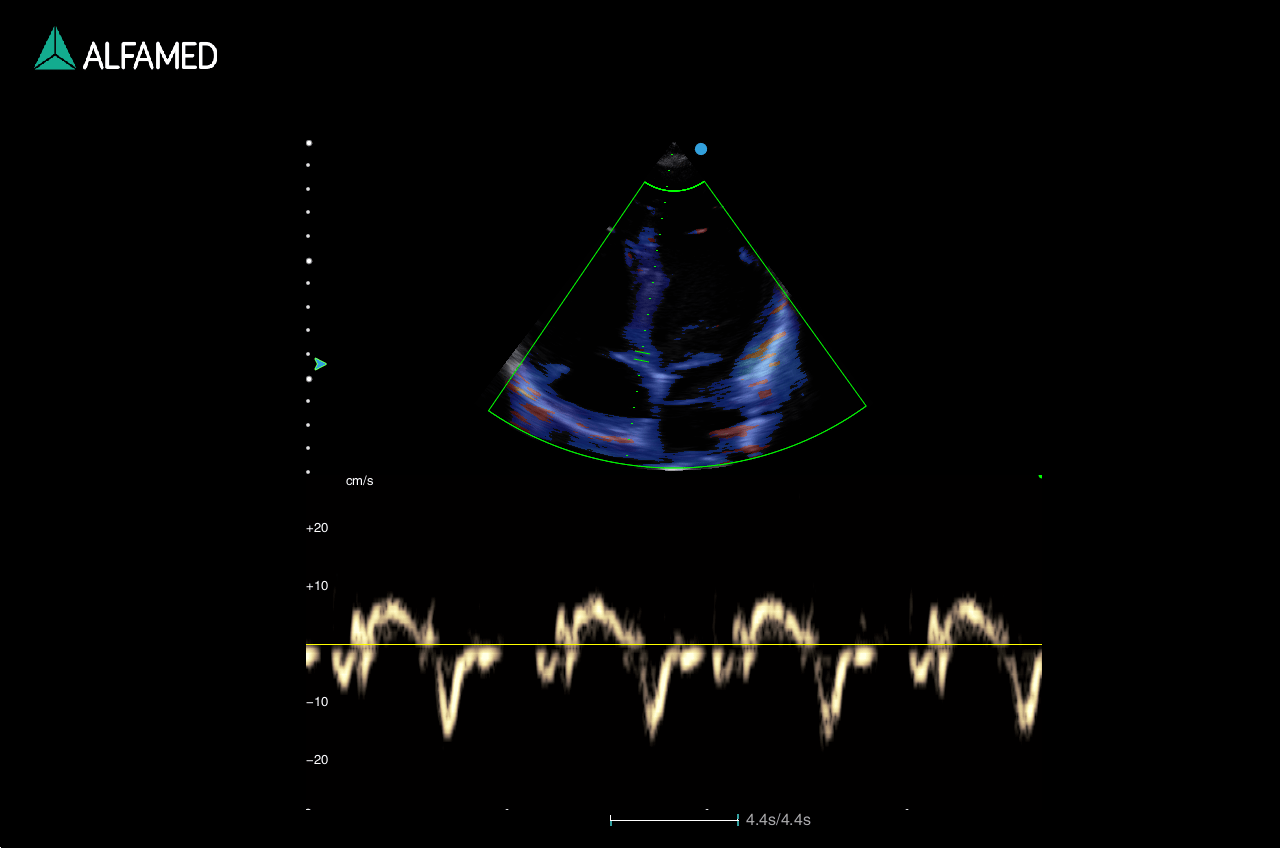

- Panoscope com Color

- TDI

- CW

- VS Flow